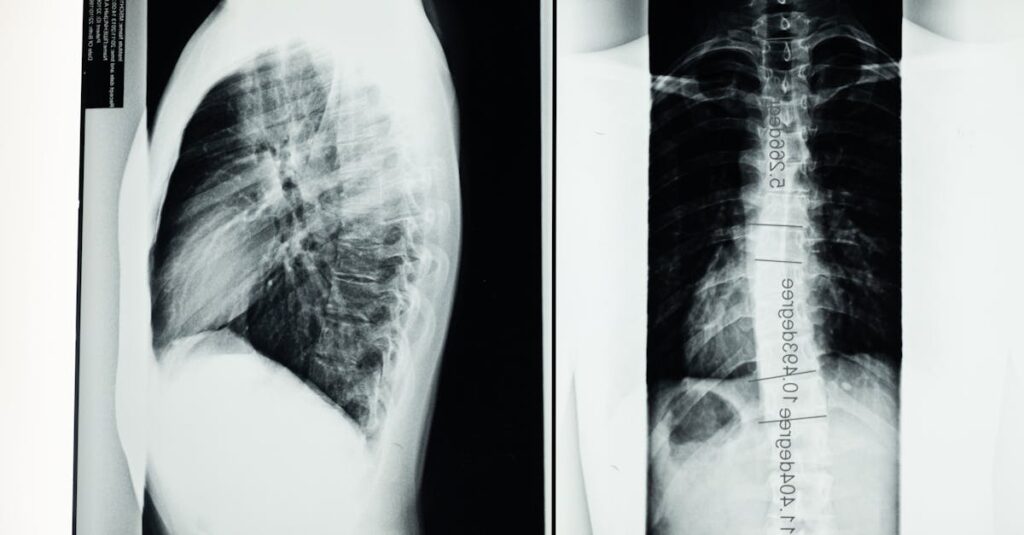

Avant de commencer un traitement de décompression vertébrale, il est crucial de réaliser une consultation approfondie. Cela inclut :

Un examen physique détaillé

Des bilans d’imagerie comme des radiographies ou IRM

La fourniture d’un historique médical complet